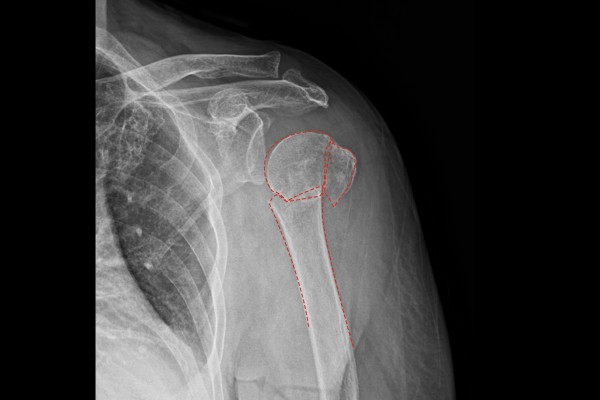

정확한 상태를 파악하기 위해 촬영한 X-RAY에서 어깨 상완골 3분위 골절이 확인 되었고,

환자분께서 들고 오신 CT 사진에서도 어깨 3분위 골절이 확인되어 어깨 상완골 근위부 골절 (3분위 골절)(Fx. proximal humerus shoulder Lt (3 part))을 진단하였습니다.

환자분의 경우 위팔뼈가 안으로 파고 들어가서 극심한 통증 및 팔의 움직임도 제한되었기에 빠른 수술적 치료가 필요하였고, 환자분께 설명 후 어깨 상완골 골절 정복술 및 금속판 고정술(ORIF plate for Fx. proximal humeus shoulder Lt)을 진행하기로 하였습니다.